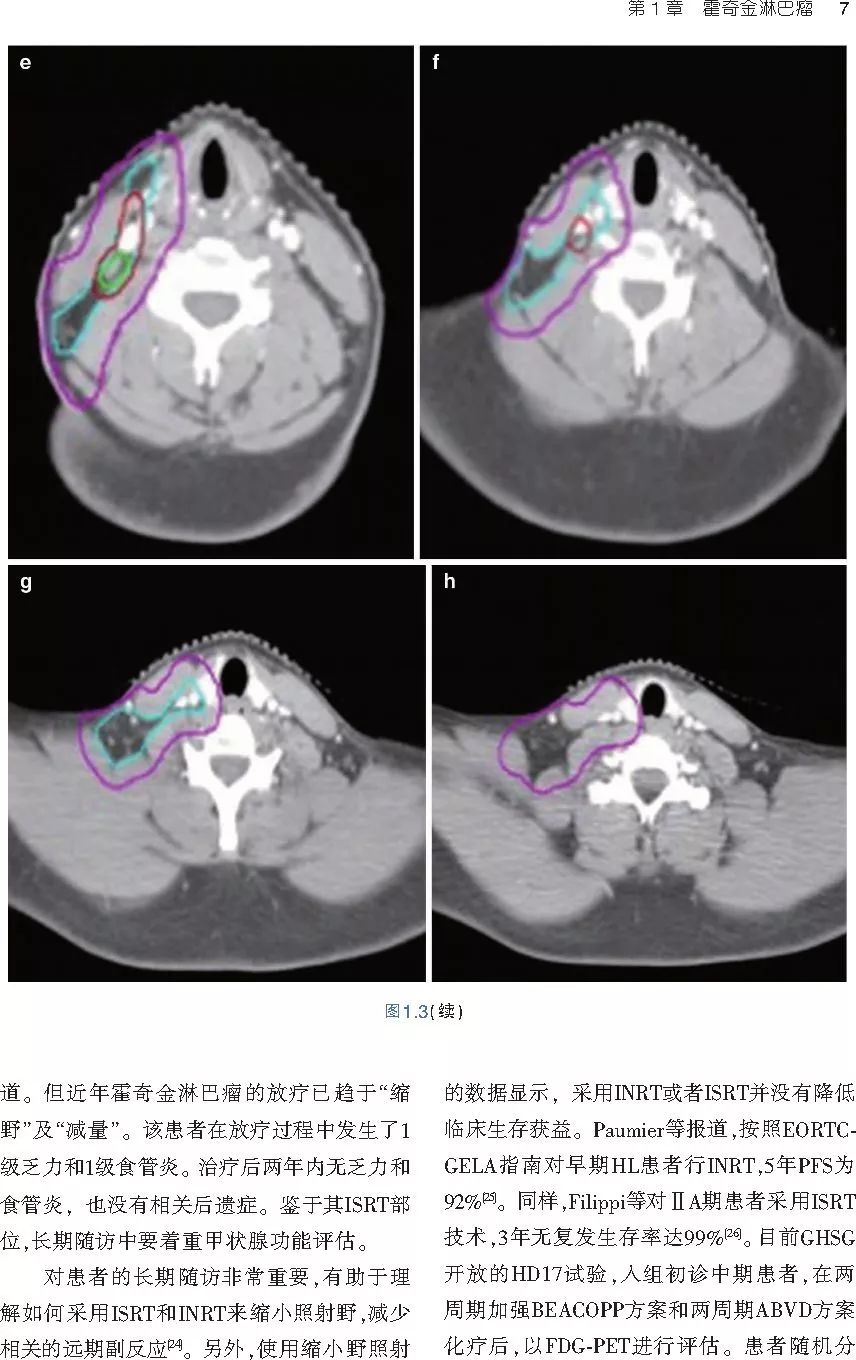

本书旨在帮助临床医生对常见血液系统恶性肿瘤疑难病例进行管理,包括霍奇金淋巴瘤、非霍奇金淋巴瘤和白血病患者,并通过多个病例进行阐述。案例讨论遵循标准格式,包括临床描述,其次是与诊断相关的病理描述和分期,然后详细讨论治疗选择。最后,确定治疗方案,并提供所使用的规划放疗技术/方式的图像。对放射肿瘤医生进行临床决策非常有帮助,针对血液病临床医生也有很好的指导作用。

近年来,放射治疗技术得到了迅速发展,调强放疗、图像引导放疗及其他新技术方法等,对恶性肿瘤治疗产生了巨大影响。现代放疗技术使精确定位、靶区勾画及给量成为可能,实现了肿瘤局控率和生活质量的双赢,对血液系统恶性肿瘤的临床治疗也产生了一定的影响。此书内容上不仅反映了血液系统恶性肿瘤综合治疗的进步,更是对其中放射治疗的新变化进行了系统、详细的阐述,这对当前血液系统恶性肿瘤放射治疗临床实践具有非常好的指导作用和参考价值。